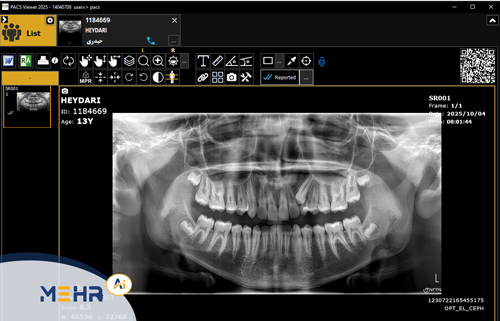

Web DICOM یک سامانه تحت‌وب برای مشاهده و مدیریت تصاویر پزشکی با فرمت DICOM است.

این سیستم به‌صورت مستقیم به سرور PACS متصل شده و امکان دسترسی بلادرنگ (Real-Time Access) به تصاویر را از طریق اینترنت فراهم می‌سازد.

پزشکان، رادیولوژیست‌ها و بیماران می‌توانند تنها با ورود به وب‌سایت مرکز درمانی، تصاویر خود را مشاهده کرده، در بزرگ‌نمایی یا کنتراست آن تغییر ایجاد کنند و در صورت نیاز، گزارش یا تصویر را به‌صورت آنلاین به اشتراک بگذارند.

۳. قابلیت مشاهده و تحلیل پیشرفته

• تنظیم روشنایی، کنتراست، بزرگ‌نمایی و چرخش تصویر

• مشاهده هم‌زمان چند سری تصویر از یک بیمار

• پشتیبانی از ابزارهای اندازه‌گیری، نشانه‌گذاری و مقایسه تصاویر